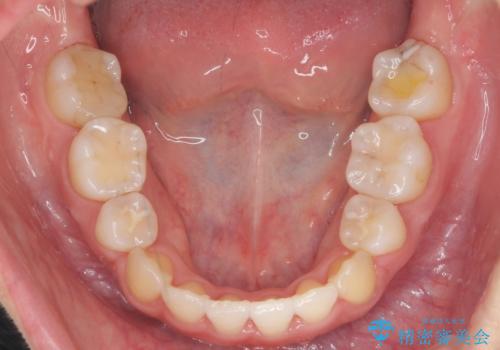

- 20代女性

- 治療計画

- 前歯のがたつきと正中のずれを主訴に来院。

小臼歯を4本抜歯しています。

歯を抜いたことで、口元が下がって、横顔も理想的なラインになりました。